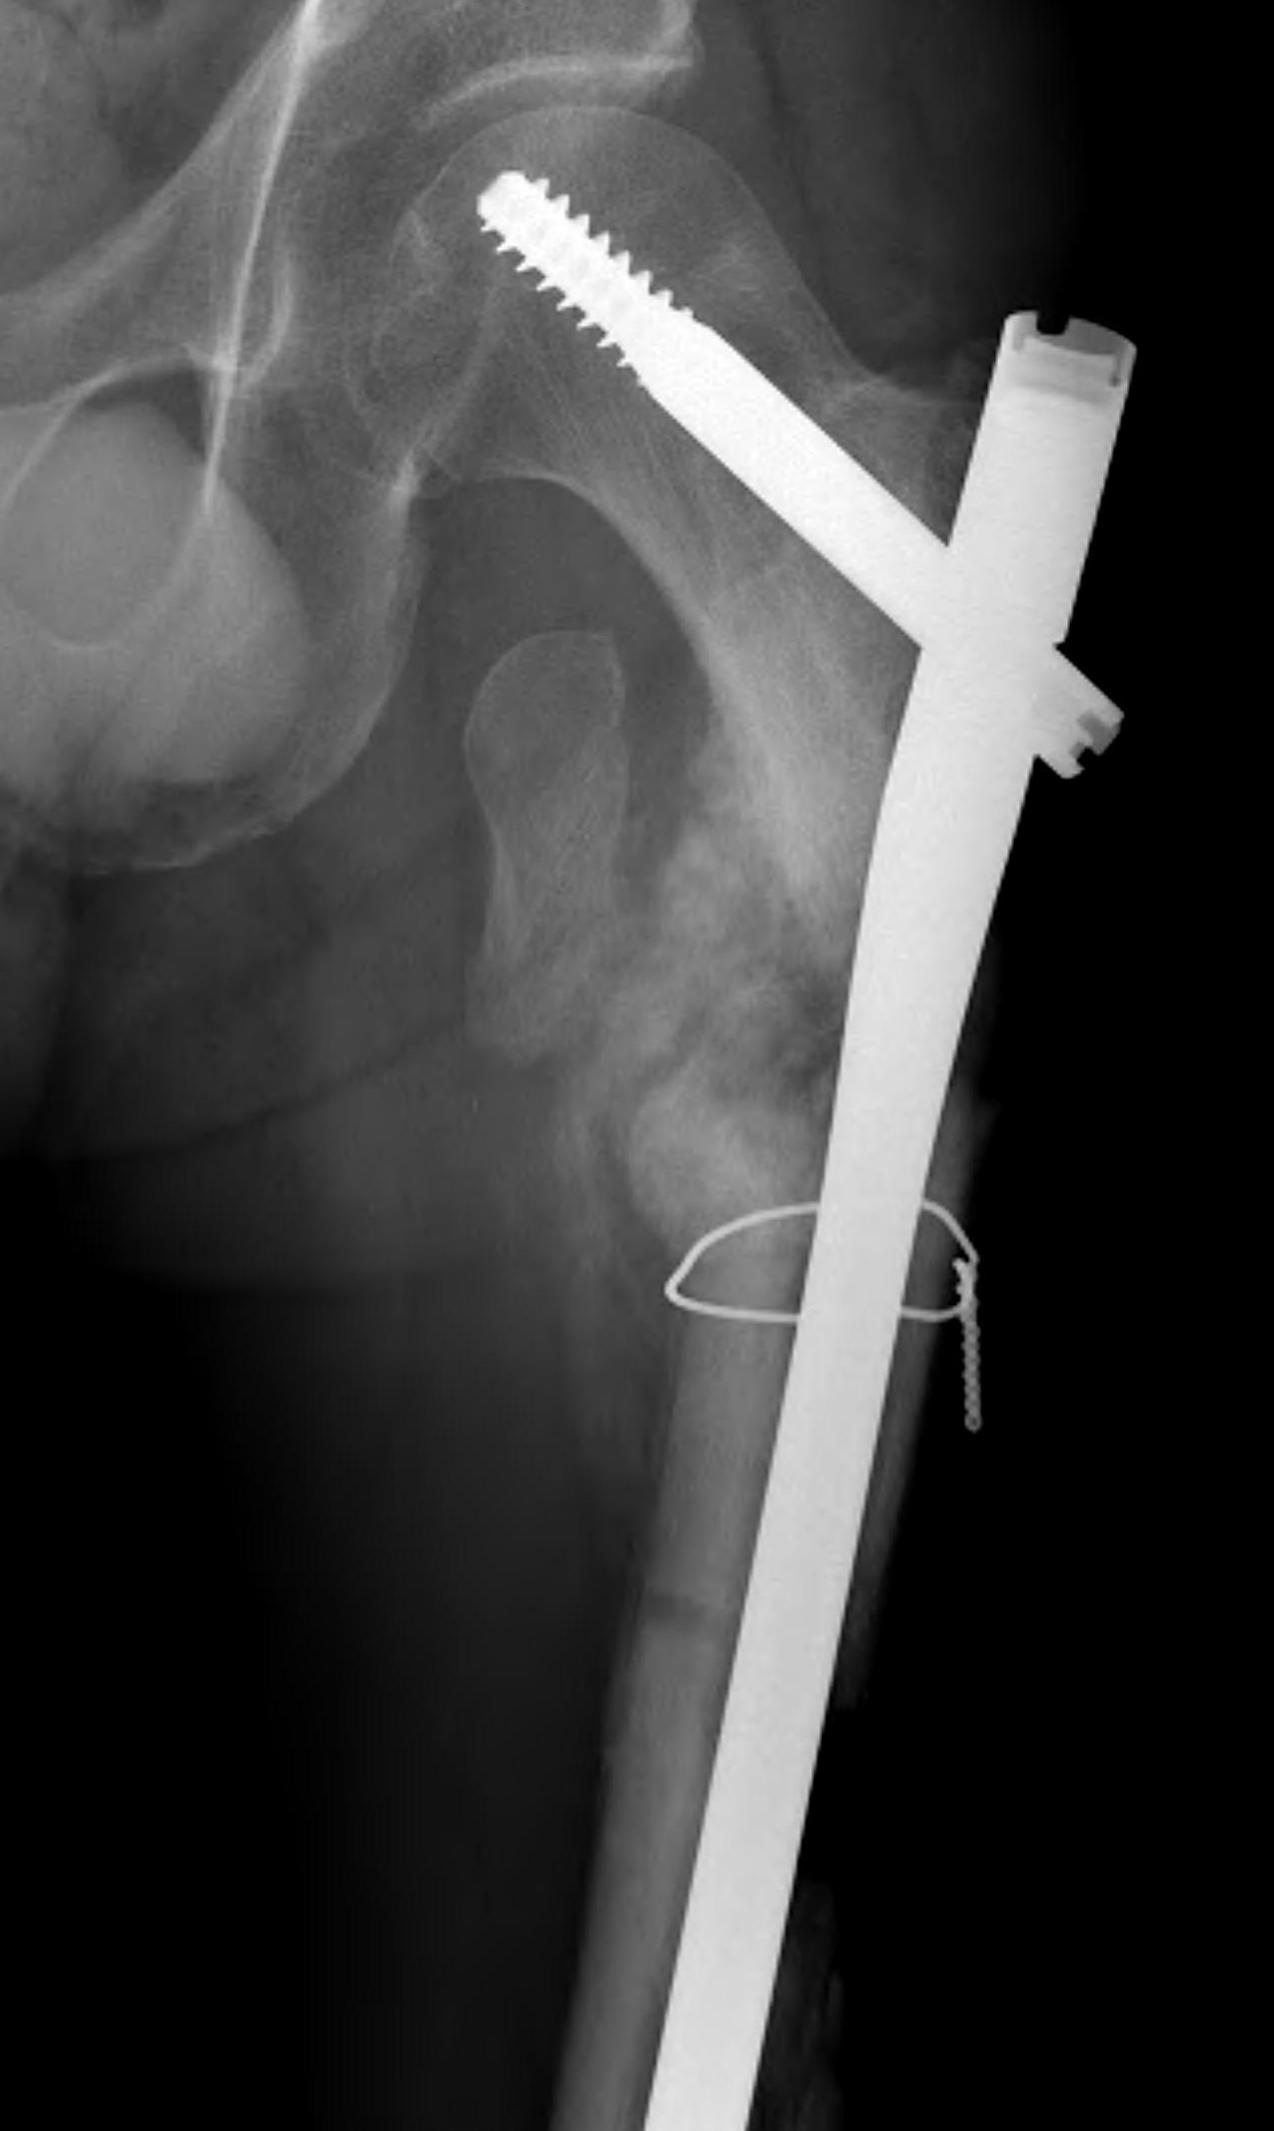

Kim et al Eur J Trauma Emerg Surg 2022

- systematic review of 14 studies and 1700 patients

- faster union and better outcome scores with cerclage wiring

- no difference in non union rates